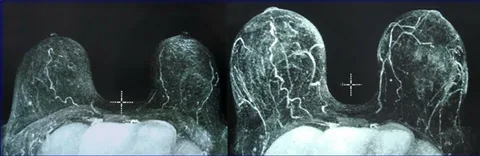

ارتداء الجهاز: قد يطلب منكِ جراحك في الرياض الاستمرار في ارتداء جهاز برافا لساعات محدودة (بروتوكول ما بعد الحقن) للحفاظ على تمدد الأنسجة وتسهيل وصول الدم للدهون الجديدة.